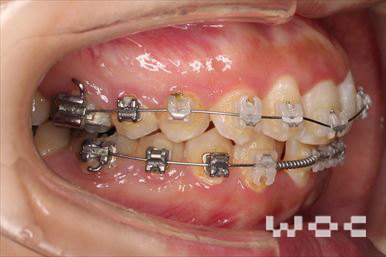

治療中1

治療中2

治療中3

治療中4

出っ歯舌側矯正

上下舌側矯正を希望。

通院状況や歯みがきの協力が良かったため、1年7ヶ月で治療を終えることができました。※装置と注意事項に関しては、大人の矯正装置一覧へ。

- 年齢:20歳女性

- 主訴:出っ歯が気になる

- 基本矯正料金:120万円

- 治療期間:1年7ヶ月

- 抜歯部位:上顎両側第一小臼歯